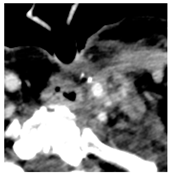

| 2 | 0–25 | 1564 | ![]() Axial CT image shows a partly necrotic tumor in the right neck. | ![]() Axial CT image obtained 18 days after injection shows the NBTXR3 nanoparticles (arrows) in the tumor. |